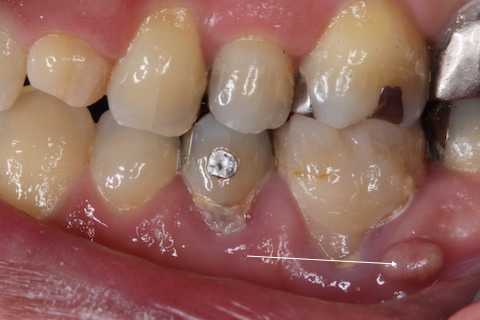

残根上のCR8 2025.10.28